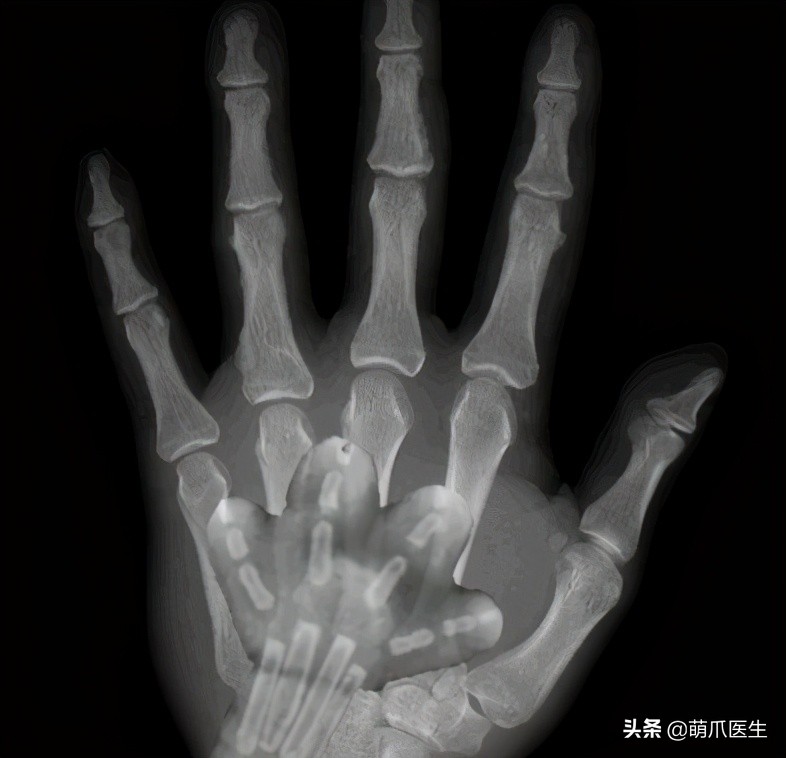

前几天,铲屎官@四月半福 发布了一段视频,居然是 她的手和猫咪爪爪的X光合影!

猫咪爪爪在X光下未免也太可爱了吧!!

随后,铲屎官在评论里解释说,合影其实是 合成的照片 。

猫爪X光片实则来自这张在网上盛传已久的图片。

但可以明确的是,猫咪骨骼发育完全时,爪爪的X光片绝对就长这样: